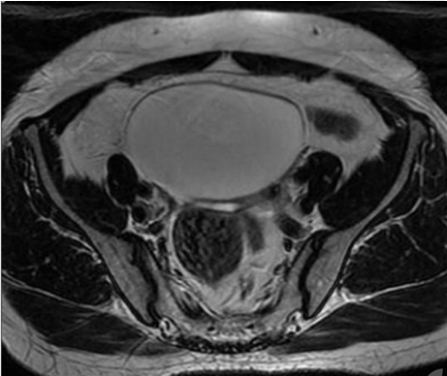

图|盆腔囊性肿块

我们都知道宫颈非典型鳞状上皮细胞,不除外高级病变(ASC-H),尤其是合并HPV感染,要特别警惕宫颈癌!看到体检报告的刘女士心里咯噔一下,害怕和担心涌上心头。为了确诊自己是不是真的得了可怕的癌症,4月21日刘女士在家人的陪伴下来到哈市某三甲医院妇瘤科就诊,进行MR检查,最终诊断结果为:“1、子宫肌瘤2、宫颈内异常结节3、双侧附件区囊性占位,考虑卵巢囊肿伴左侧输卵管扩张”。